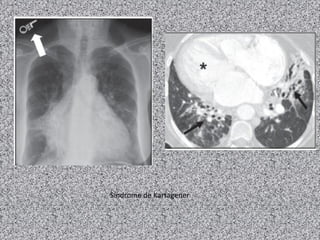

Metade dos casos é associdas a situs inversus

(síndrome de Kartagener):

Combinação de situs inversus, sinusite crônica e

bronquiectasias.

Radiografia de tórax:

Normal ou achados não específicos como

espessamento brônquico e aumento da trama

broncovascular;

Dextrocardia e situs inversus em 50% dos casos;

Sinais de bronquiectasias.

TCAR de tórax:

Bronquiectasias (achado principal) geralmente do

tipo cilíndrico;

Nódulos centrolobulares e opacidades lineares ou

ramificadas;

Áreas de diminuição da atenuação e perfusão e

aprisionamento aéreo à expiração.

Síndrome de Kartagener